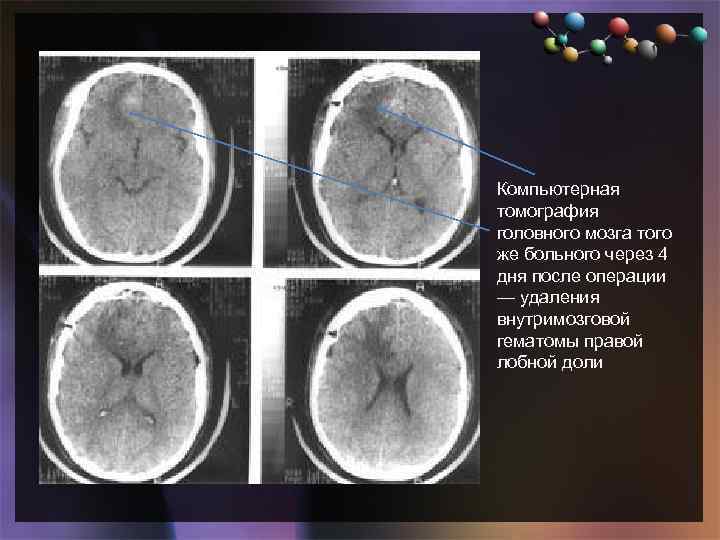

• Подзаголовок слайда Компьютерная томография головного мозга того же больного через 4 дня после операции — удаления внутримозговой гематомы правой лобной доли

• Подзаголовок слайда Компьютерная томография головного мозга того же больного через 4 дня после операции — удаления внутримозговой гематомы правой лобной доли